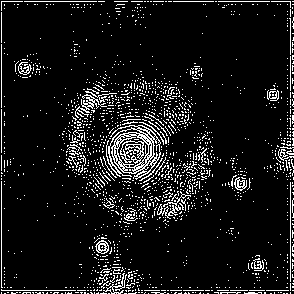

Original frames was obtained from U-118 cell line sample set. U-118 is human glyoblastoma cells widely used as model for drug testing. Also it has fibroblast like morphology and highly dynamic shape change pattern. From original microscopic images we created sets of frames containing single cell with manually outlined borders as ground truth dataset. This sets were used to have primary evaluation of segmentation successiveness. In result of described batch segmentation we obtained outline masks for each image in sequence with different accuracy of segmentation. Frames 1, 2, 9, 15, 20, 25, 40 of U-118 cell line sequence at Fig.2 an example of drastic changes of segmentation accuracy compared to manual perimeter detection.

Figure 2: Original images sample sequence, results of algorithm processed and manually outlined cell contour. The image i and j of sequence show bad segmentation accuracy compared to manually outlined images, while rest of sequence has acceptable level.